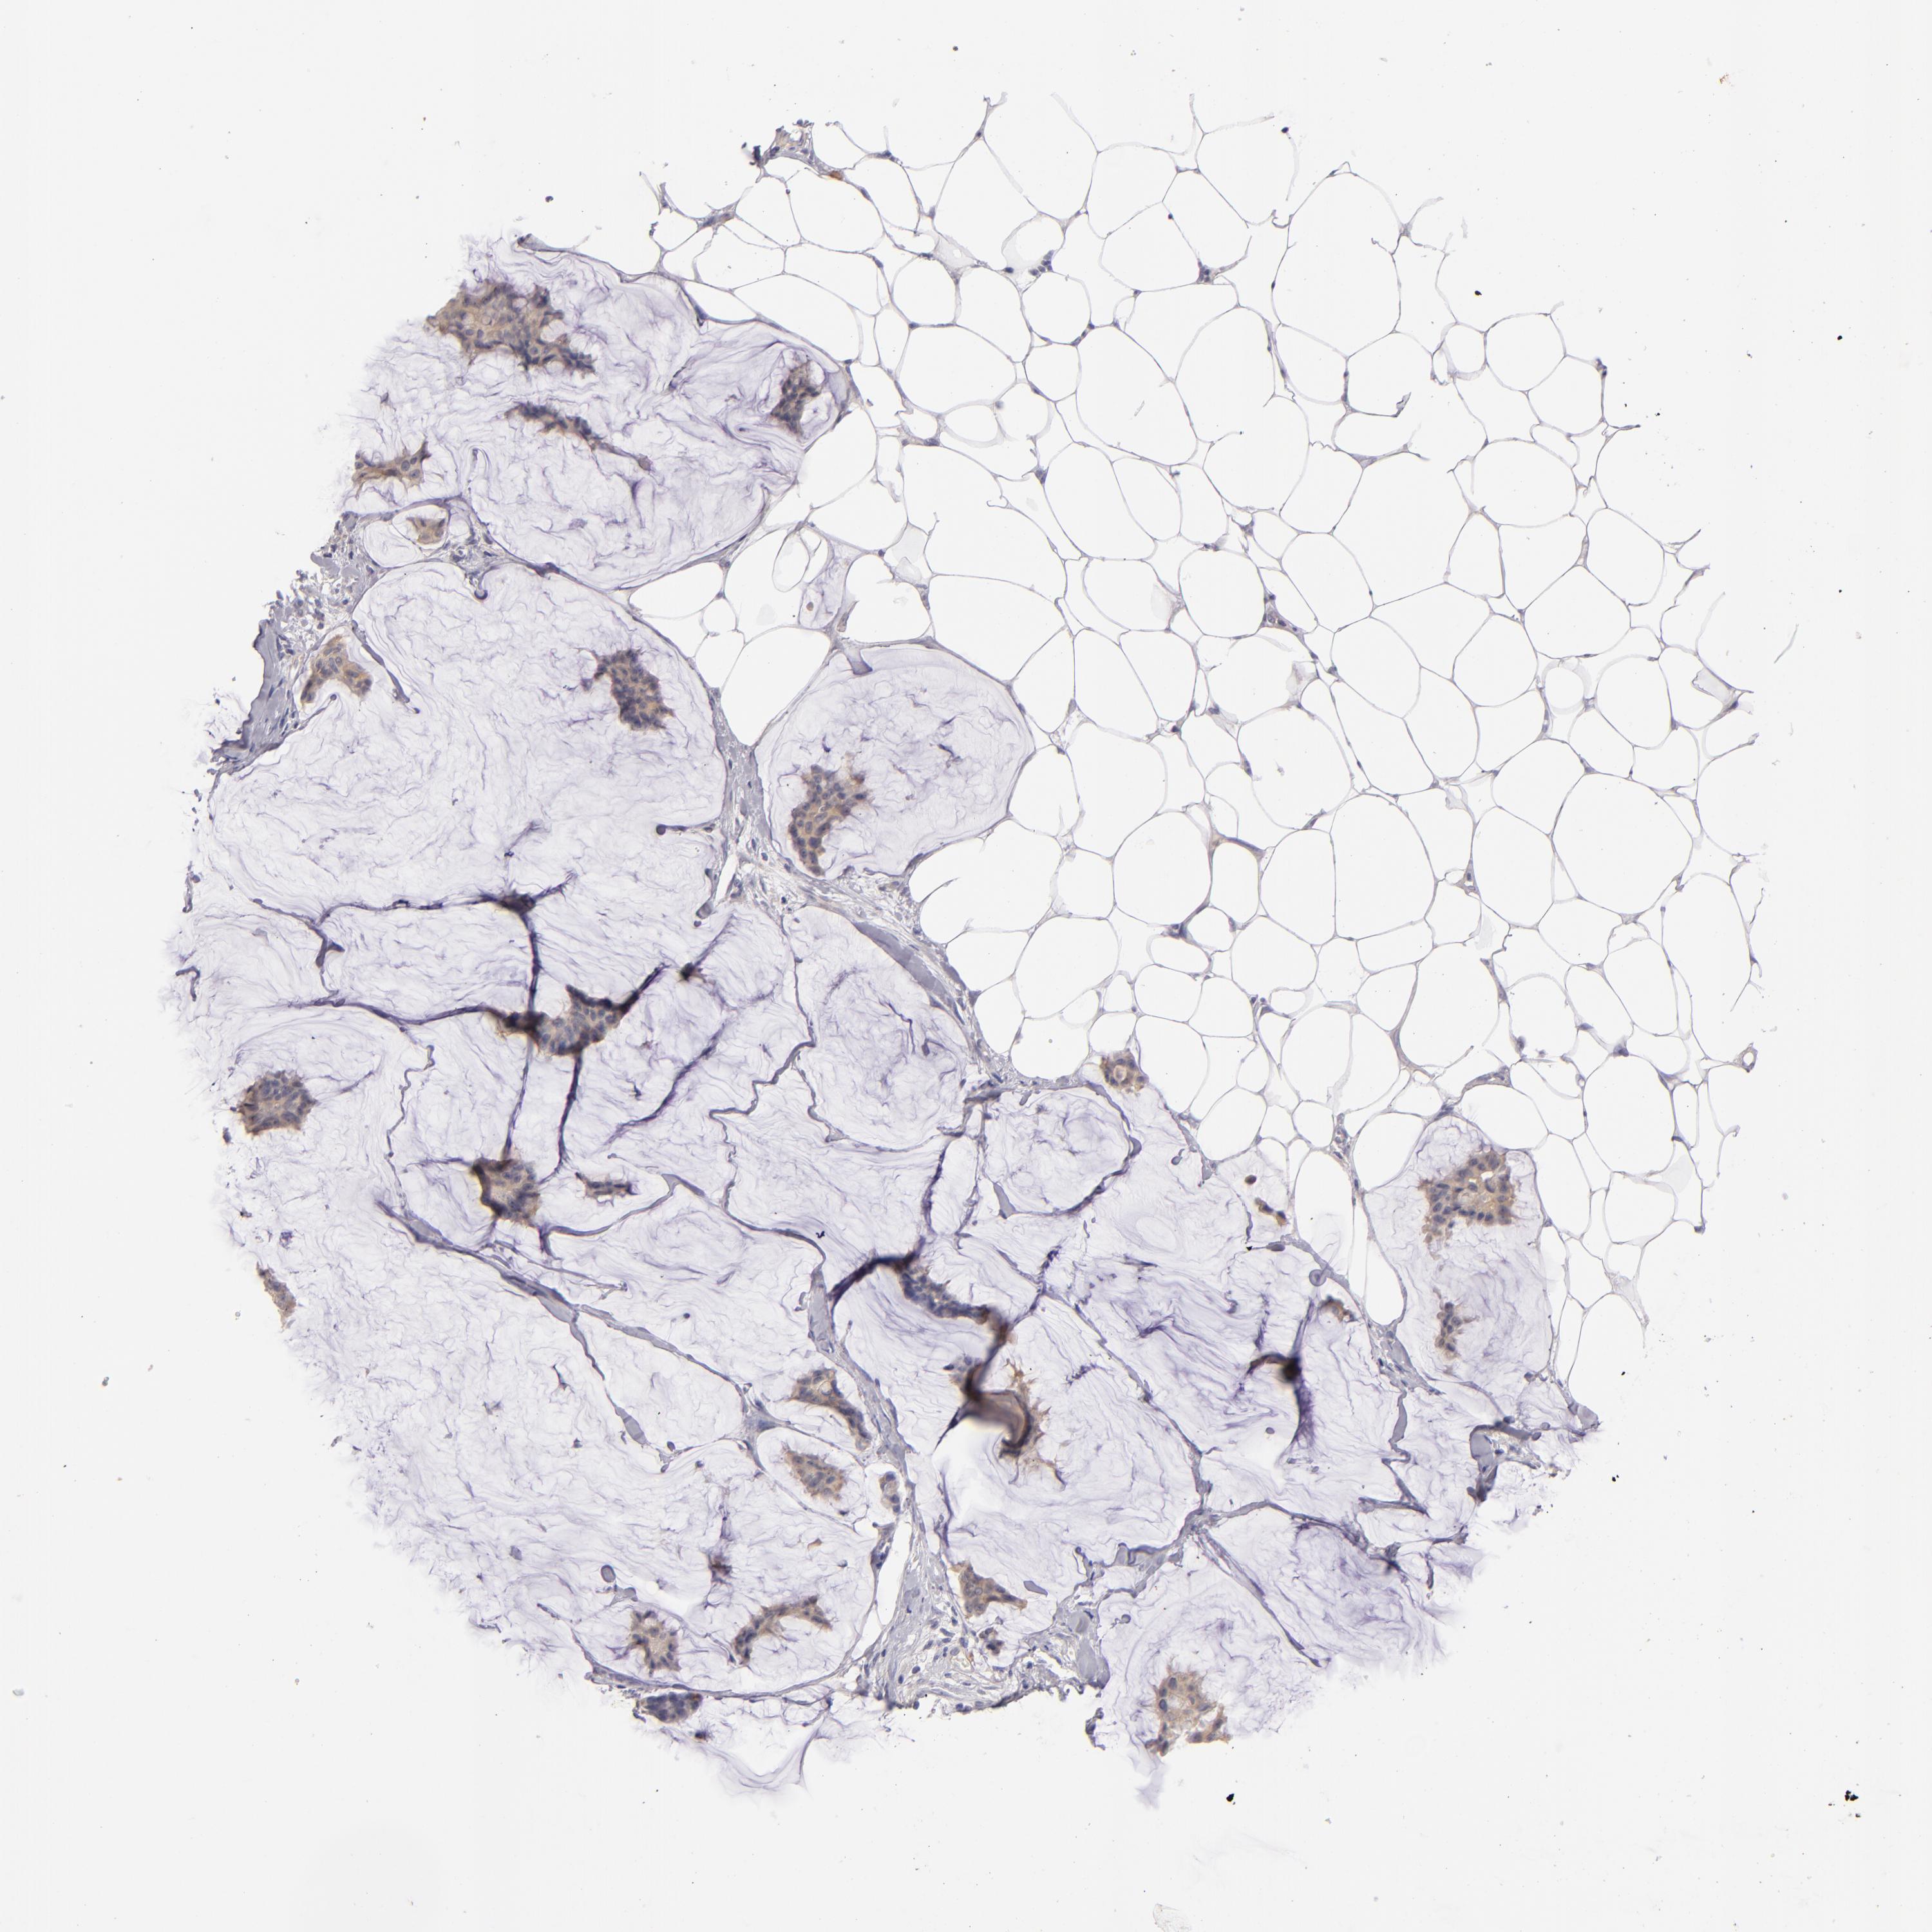

BRCA TCGA BRCA VALIDATION PROTEIN EXPRESSION

Breast cancer

Human cancer